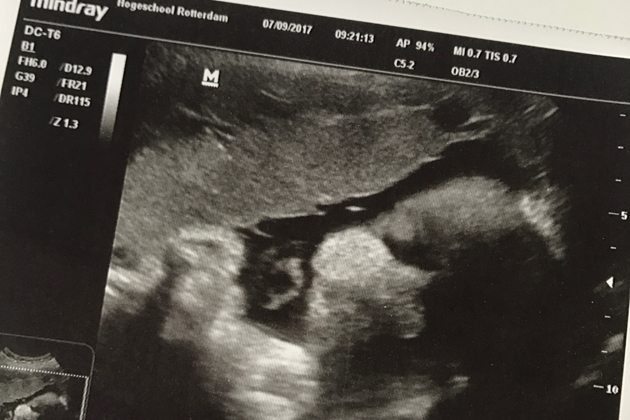

Met een mooie foto van haar gezichtje en een goed gevoel (ik had immers bijgedragen aan ‘de wetenschap’) reed ik weer naar huis om m’n werkdag te vervolgen. Wat een fijne ochtend.